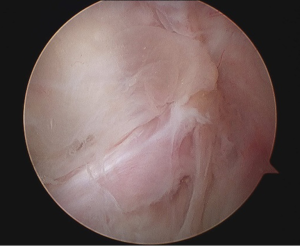

Arthroscopy revealed that the large ACL ganglion cyst was both intra-substance and extending in the posterior direction (Figures 2,3). A posteromedial portal was created to assist in visualising the ganglion from the back of the knee and to allow complete excision. The content consisted of a yellowish gelatinous material (Figure 4).